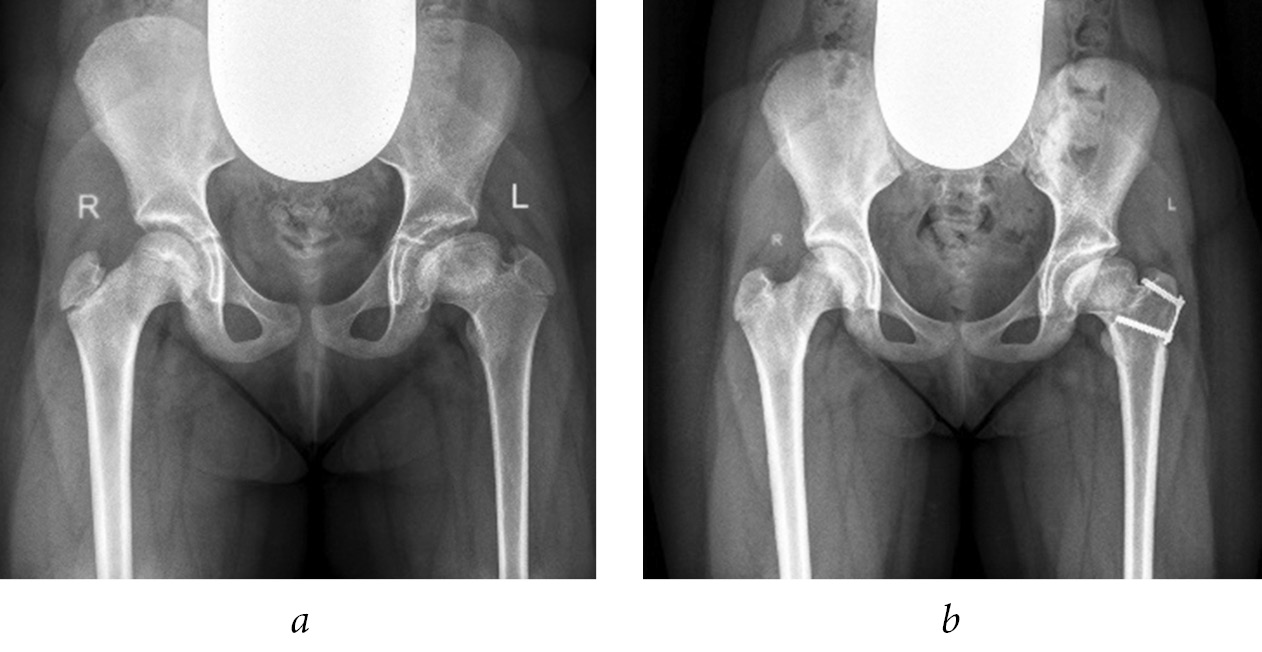

To exclude displacement of the greater trochanter, adherence to bed rest, or use of ambulation support in the postoperative period, before the destruction of the growth zone, the greater trochanter was fixed to the femur using an eight-shaped plate with screws or a cortical screw with a washer. The eight-shaped plate was installed from the lateral surface of the hip, and the cortical screw was inserted from the superior lateral parts of the greater trochanter toward the lesser trochanter parallel to the intertrochanteric line of the femur (Figs. 1, 2) [19].

Fig. 2. Radiographs of patient G (4 years old) diagnosed with complications of septic arthritis of the hip joint, emerging high position of the greater trochanter on the right, and multiplanar deformity of the femoral neck with eccentric growth of the epiphysis posteriorly: a, b, before surgery; c, immediately after trochanteric epiphysiodesis on the right